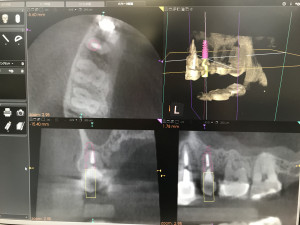

治療計画したインプラント埋入位置をデータ化してそれを3Ⅾプリンターに送るのです。このデータと、実際の口の中のデータ(現在は歯型模型)をPC上で融合させるのです。そうするとサージカルステントといってインプラント手術用の重要な道具を作ることが出来ます。いわばこれは「物差し」です。

実際のインプラント手術をする際に、このサージカルステントを口腔内にパチっとはめ込むとガイドリングがついていてインプラントの位置と埋入深度(深さ)が決まります。